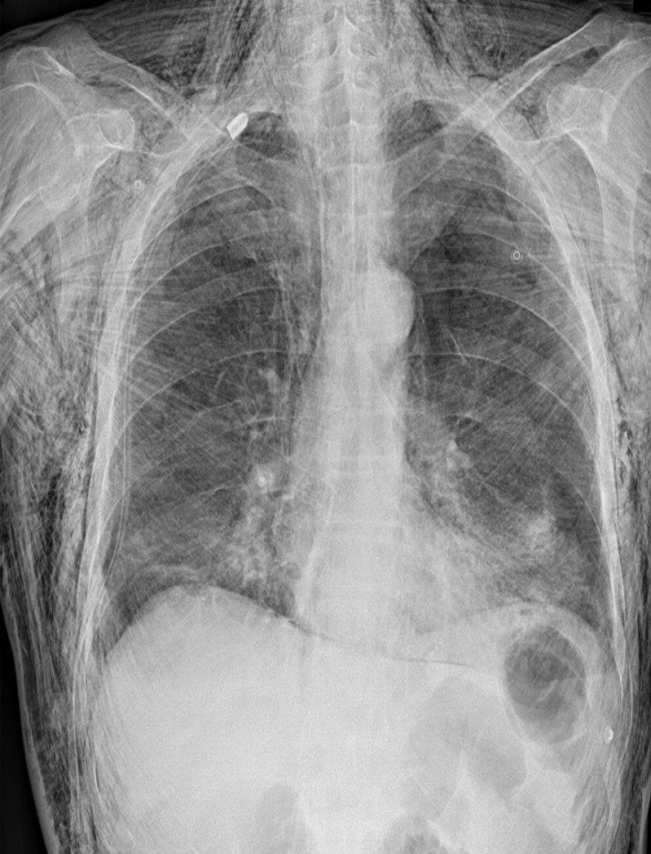

A. What is the most likely diagnosis in the given images

pneumonia ex… due fever cough and the imaging

B. Which lobe of the lung affected by this disease in the given image. Right middle Lobe Lesion, due obliteration of diaphragm - and lateral of horizontal fissure opaque

Pneumonia most common due to no deviations of midline - could be truama, ectopy, etc… so follow through with case given for diagnosis